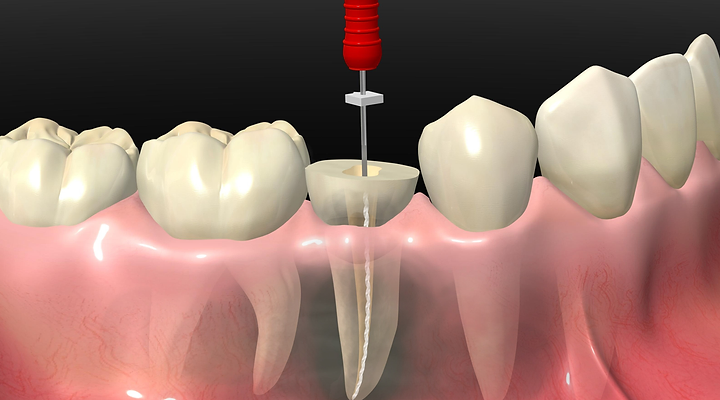

EnDODONCIA